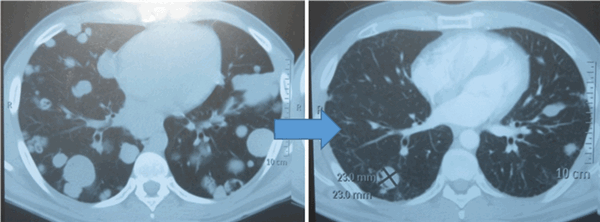

Показания к химиотерапии определяются степенью распространенности процесса, наличием легочных/внелегочных метастазов. Стандартным режимом химиотерапии при герминогенных опухолях является режим «BEP», включающий блеомицин, этопозид и цисплатин. Для пациентов с дыхательной недостаточностью, обширным поражением легких, во избежание легочной блеомициновой токсичности, как альтернативный вариант, может быть использованы режимы химиотерапии VIP (этопозид, ифосфамид, цисплатин) или ЕР (этопозид, цисплатин).

Для оценки эффективности химиотерапии каждые 2 цикла и после ее окончания проводится компьютерная томография исходных зон поражения, перед каждым циклом мониторинг уровня опухолевых маркеров. Рост маркеров на фоне лечения или после его завершения, а также замедление их снижения свидетельствует об активности опухолевого процесса и необходимости проведения второй линии химиотерапии.

![Метастазы в легких до лечения и после 4х циклов химиотерапии по схеме «ВЕР» (КТ грудной клетки)]()

Метастазы в легких до лечения и после 4х циклов химиотерапии по схеме «ВЕР» (КТ грудной клетки)

При проведении химиотерапии необходимо регулярно оценивать ее эффективность. Для этого каждые 2 цикла и после ее завершения проводится КТ тех областей, которые изначально были поражены опухолями. Также перед каждым циклом проверяется уровень онкомаркеров в крови. Если на фоне терапии или после ее окончания уровень онкомаркеров растет либо замедляется его снижение, то это говорит о том, что опухолевый процесс активен и нужно проводить вторую линию химиотерапии.